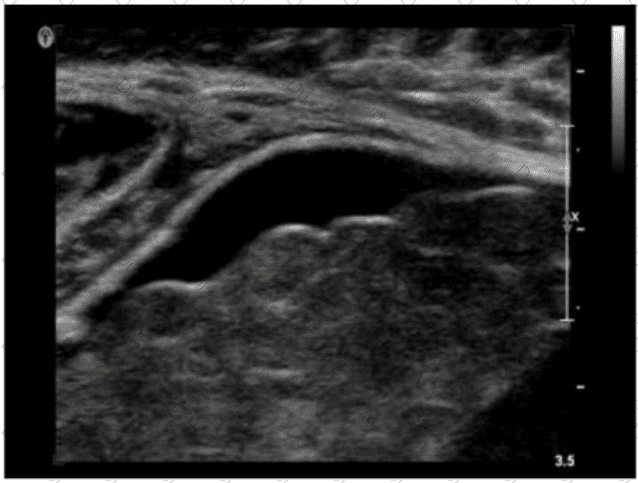

Which vascular condition is most likely associated with the sonographic findings demonstrated in this image?